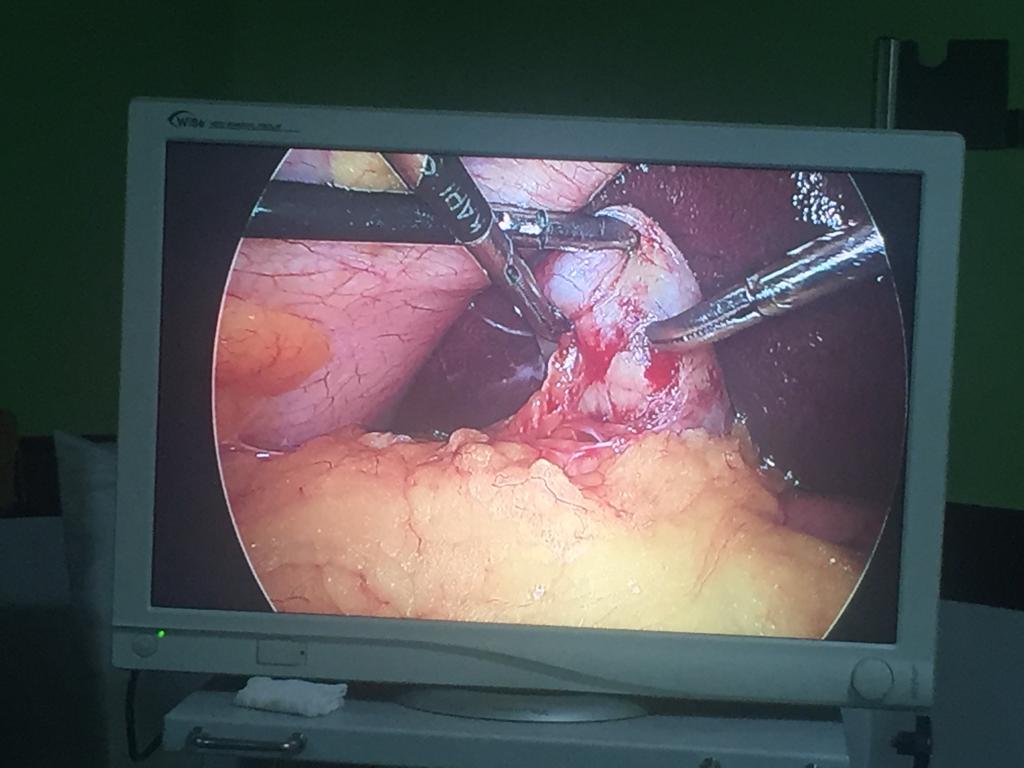

Laparoscopic right inguinal hernia mesh repair ( TAPP )

Complex abdominal wall ventral hernia done completely done Laparoscopically ( e-TEP/ RS/ UL TAR )